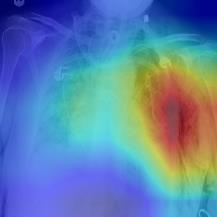

Thoracic disease detection from chest radiographs using deep learning methods has been an active area of research in the last decade. Most previous methods attempt to focus on the diseased organs of the image by identifying spatial regions responsible for significant contributions to the model's prediction. In contrast, expert radiologists first locate the prominent anatomical structures before determining if those regions are anomalous. Therefore, integrating anatomical knowledge within deep learning models could bring substantial improvement in automatic disease classification. This work proposes an anatomy-aware attention-based architecture named Anatomy X-Net, that prioritizes the spatial features guided by the pre-identified anatomy regions. We leverage a semi-supervised learning method using the JSRT dataset containing organ-level annotation to obtain the anatomical segmentation masks (for lungs and heart) for the NIH and CheXpert datasets. The proposed Anatomy X-Net uses the pre-trained DenseNet-121 as the backbone network with two corresponding structured modules, the Anatomy Aware Attention (AAA) and Probabilistic Weighted Average Pooling (PWAP), in a cohesive framework for anatomical attention learning. Our proposed method sets new state-of-the-art performance on the official NIH test set with an AUC score of 0.8439, proving the efficacy of utilizing the anatomy segmentation knowledge to improve the thoracic disease classification. Furthermore, the Anatomy X-Net yields an averaged AUC of 0.9020 on the Stanford CheXpert dataset, improving on existing methods that demonstrate the generalizability of the proposed framework.